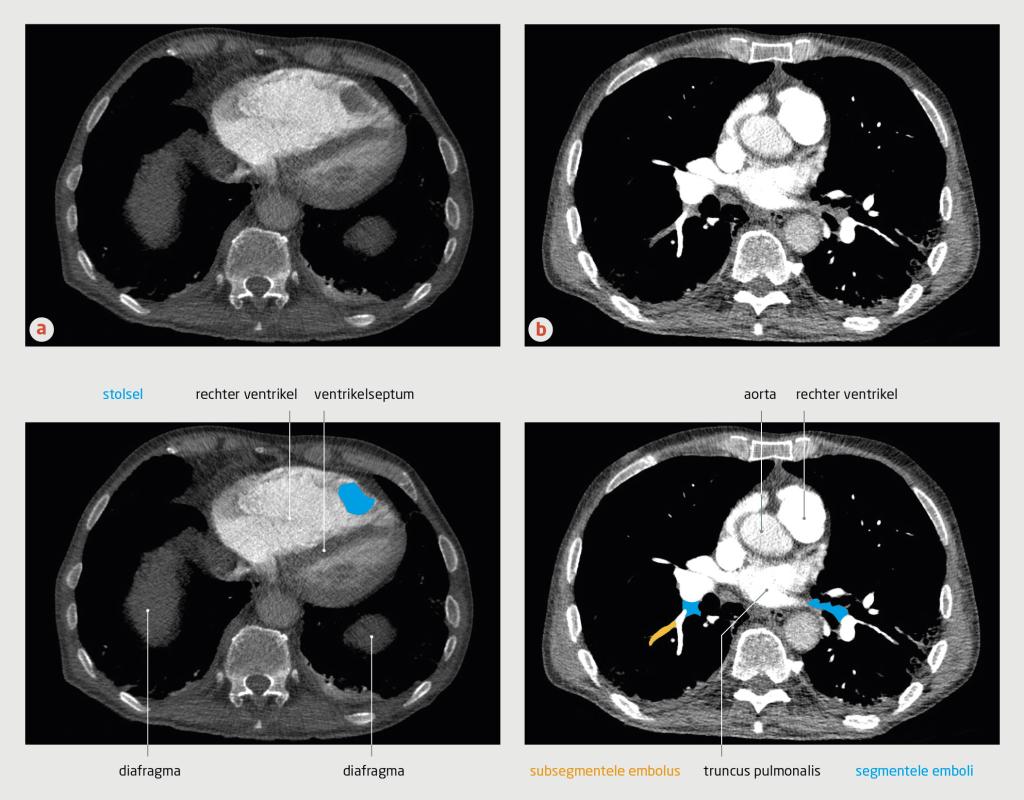

Figuur 3

CT-angiografie van de thorax van patiënt C

CT-angiografie met contrast van patiënt C (transversale coupe). (a) In de rechter ventrikel bevindt zich een stolsel. De rechter ventrikel is vergroot en er is sprake van septumdeviatie, passend bij overbelasting van de rechter ventrikel. (b) Bij deze patiënt was sprake van subsegmentele longembolieën.

Gezien dit klinische beeld, de D-dimeerwaarde van 3,3 mg/l en een sterke verdenking op longembolie werd op grond van het YEARS-algoritme (afkapwaarde voor D-dimeer: 0,5 mg/l) een CT-A verricht. Deze liet multipele segmentele en subsegmentele longembolieën zien, alsmede een stolsel in de apex van de rechterventrikel met een diameter van 3 cm (figuur 3).